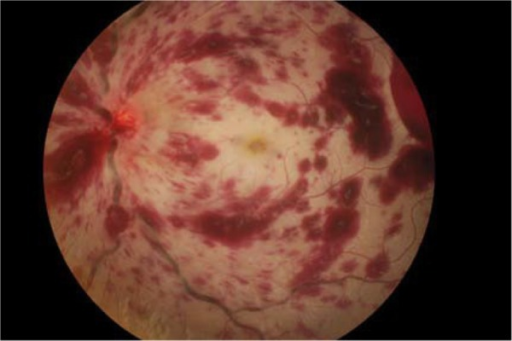

CRVO

| 출혈 | 경도-중등도 | 광범위 4사분면 |